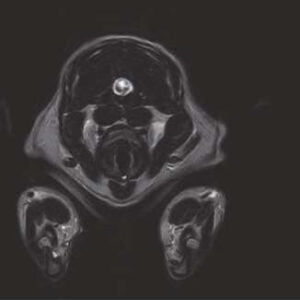

The PANION PRO comes with the double-pole open magnet design with a wide opening gap of 40 cm to accommodate large-sized animals on an efficient patient handling platform, the strongest gradient amplitude at 33mT/m and slew rate of 90 T/m/s, among all other open MRI systems, resulting in high spatial resolution of images in short scan time. The 6-direction patient table permits iso-centre imaging of all anatomical regions.

Clinical Images